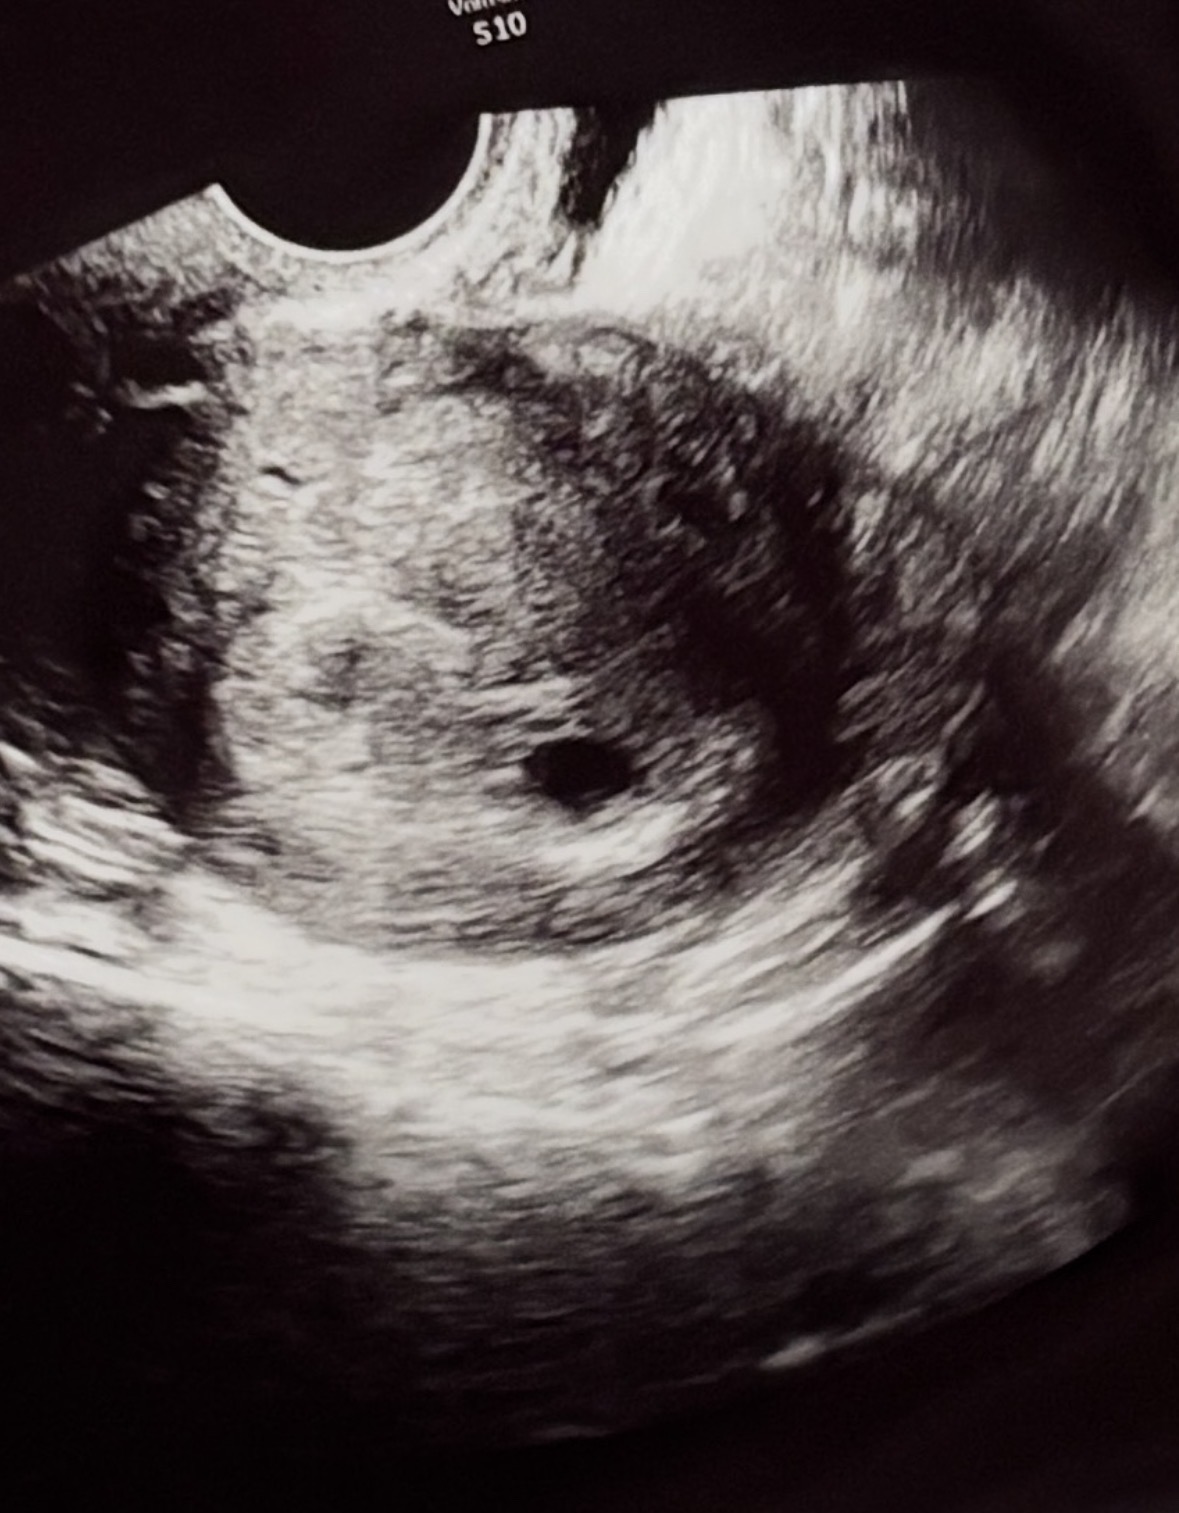

아기집 봐주세요!

막생이 10월 27일이라 이걸로 계산해보면 6주6일인데 의사선생님이 6주까지는 아니라고 하시더라구요. 초음파는 12월13일에 찍고 27일에 심장소리가 들려야한다라고 하셨는데, 다른 얘기 없으시면 잘 크고있는거겠죠..?ㅠ 이번주에 서브병원에 가봐도 되는걸까요?

감기기운이 심해서 오늘 병원 다녀왔는데 3일만에 아기집은 2배로 커져있고 난황도 보고왔어요! 괜한 걱정이였나봐요😂